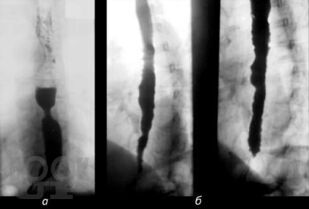

В книге изложены основные сведения по анатомии и патофизиологии пищевода и кардии, освещены вопросы клиники, диагностики, консервативного и оперативного лечения их хирургических заболеваний. С учетом последних достижений медицинской науки и практики описаны нервно-мышечные заболевания пищевода, гастроэзофагеальная рефлюксная болезнь, злокачественные новообразования, травмы, ожоги, болезни оперированного пищевода. Особое внимание уделено хирургической тактике и технике оперативных  вмешательств.